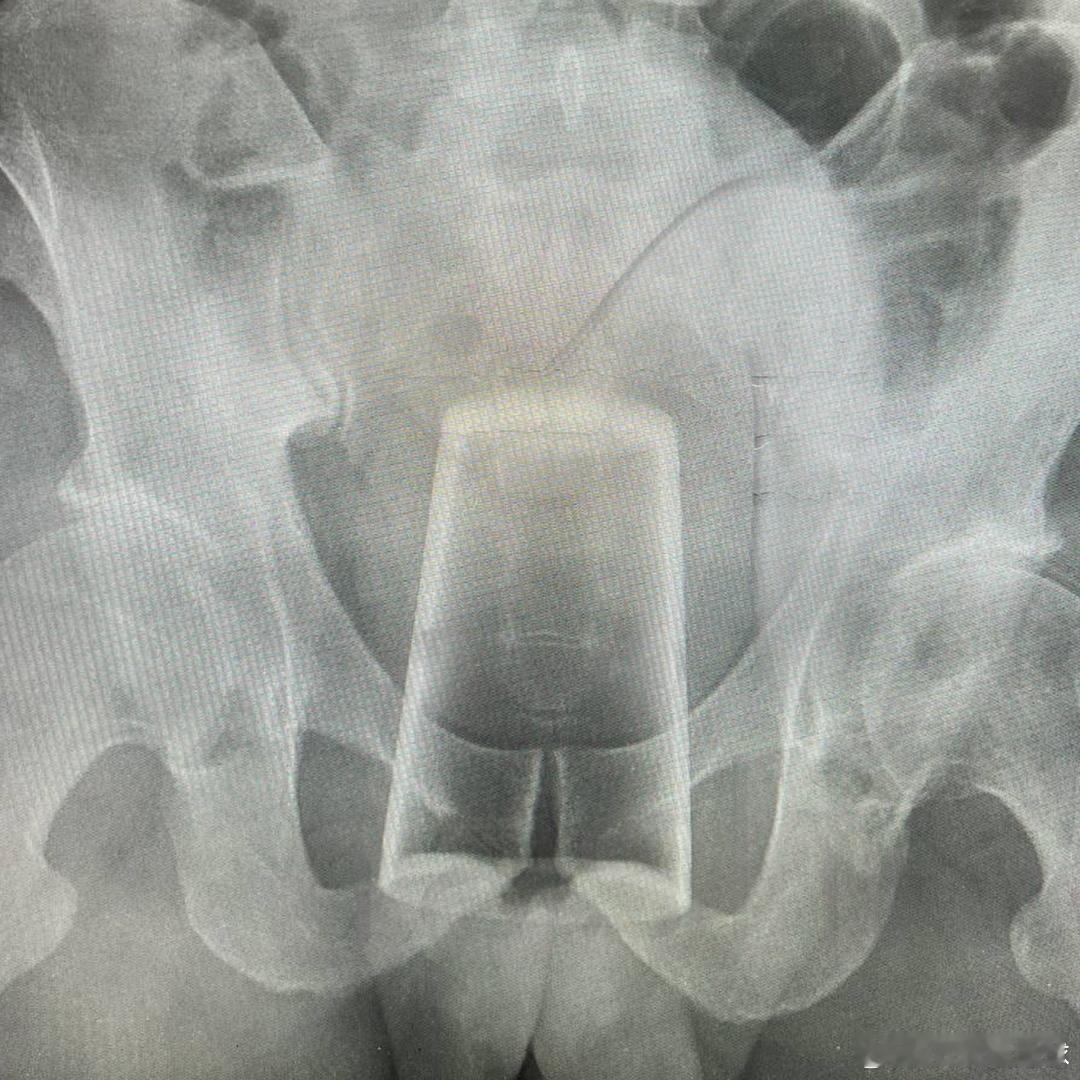

一俄罗斯男子不知怎么把玻璃杯卡进了屁股里。他声称自己是滑倒了,不小心坐到了杯子上。他当时刚好没穿裤子,杯子刚好没有碎掉他自己尝试把杯子取出来但失败了,最后只能求助医护人员。大千世界无奇不有海外新鲜事